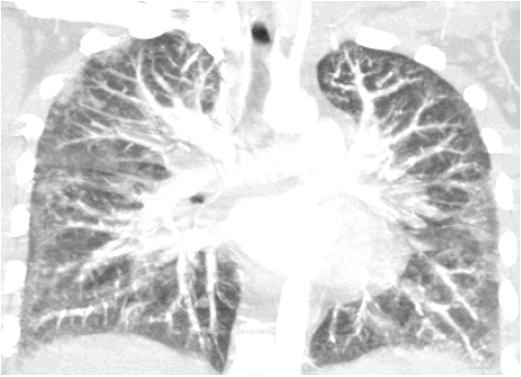

Electrocardiogram showed sinus tachycardia. Chest radiographs showed bilateral reticulonodular infiltrates, mainly basal in distribution, with blunting of the costophrenic angles (Figure 1). Computed tomography (CT) angiography with contrast showed bilateral subpleural ground-glass lobular infiltrates with bilateral hilar lymphadenopathy (Figure 2).

Figure 2. Computed tomography angiography with contrast at initial presentation showed bilateral subpleural ground-glass lobular infiltrates with bilateral hilar lymphadenopathy.